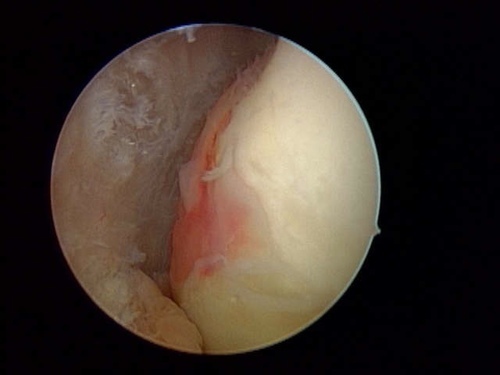

隱藏病灶                                                         手術清除中                                                      清除後